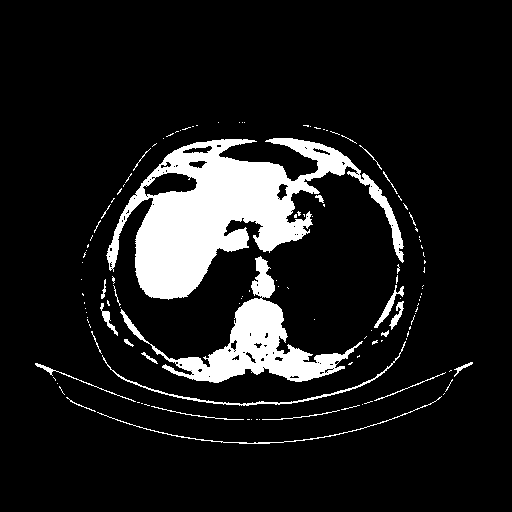

Reconstructed NATIVE CT scan (cycle consistency)

Full window (WL 1023.5, WW 4095 β†’ Low βˆ’1024, High +3071)

Actual HU range: [-1024.0, 3071.0]